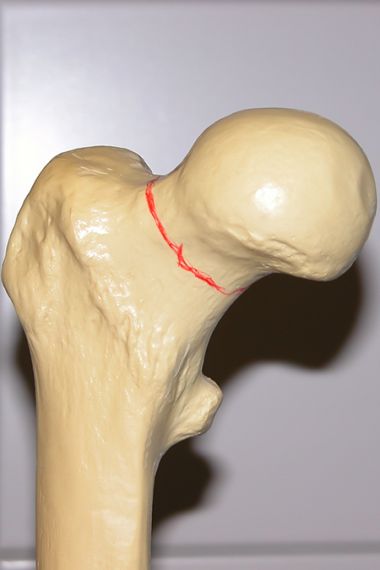

Bei einer Schenkelhalsfraktur verläuft der Bruch unmittelbar unterhalb des Hüftkopfes. Je nach Bruchverlauf (Pauwels Klassifikation) und Grad der Verschiebung (Garden Klassifikation) kommen sowohl den Bruch stabilisierende Verfahren mit Erhalt des körpereigenen Hüftkopfes, als auch kopfersetzende Operationsverfahren (künstliches Hüftgelenk) zur Anwendung. Immer ist das Ziel, ein stabiles, belastbares Hüftgelenk herzustellen, da das Hüftgelenk selbst schon beim Aufrichten aus der liegenden Position im Bett mit annähernd Körpergewicht belastet wird.

Deutliche Knochenstufe am Schenkelhals

rechtsseitige Schenkelhalsfraktur